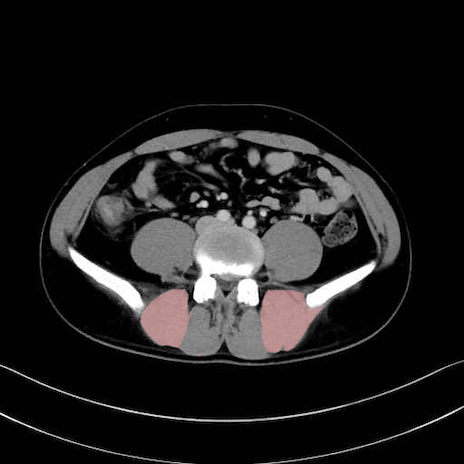

内閉鎖筋 (Obturator internus)